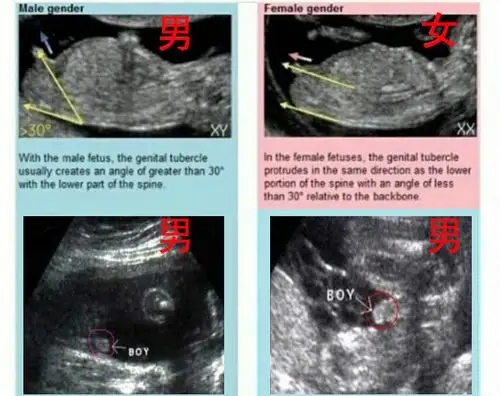

胎儿12周